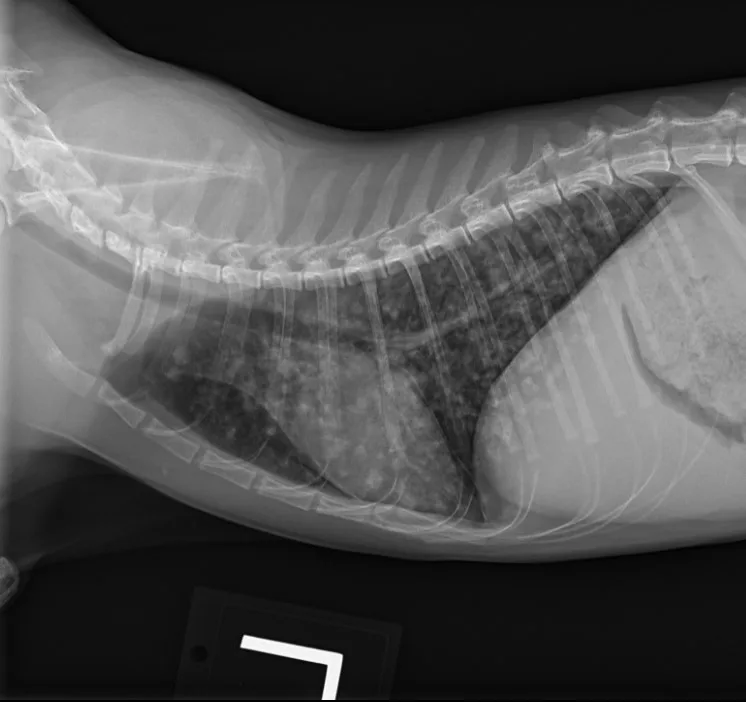

Butorphanol (0.2 mg/kg IV) was administered for sedation to obtain 3-view thoracic radiographs (left lateral, right lateral, ventrodorsal). Results revealed diffuse pulmonary nodular changes with an underlying bronchointerstitial pattern (Figure 1). Fungal pneumonia, parasitic pneumonia, neoplasia, and eosinophilic inflammatory disease were the most likely differentials for this pattern.

A

FIGURE 1 Left lateral (A), right lateral (B), and ventrodorsal (C) thoracic radiographs at the time of initial diagnosis. Diffuse pulmonary nodular changes with an underlying bronchointerstitial pattern can be seen.